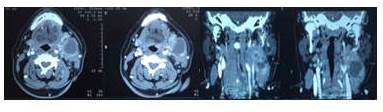

Acude a médico en otro centro asistencial quien describe que al examen físico evidencia lesión de aproximadamente 4 cm de diámetro, ubicada en el triángulo anterior de cuello, anterior al músculo esternocleidomastoideo en su tercio superior, procediendo a realizar estudio tomográfico (Figura 1,2 y 3) y exéresis del mismo.

Es evaluado por nuestro centro, donde se realiza anamnesis y posteriormente el examen físico, exhaustivo incluyendo nasofibrolaringoscopia no evidenciando tejido amigdalino palatino ni lesiones en el tracto aéreo digestivo superior. Al tacto intraoral, de orofaringe incluyendo base de lengua, no se palpaban lesiones. Se observa estudio de TAC de cuello con contraste intravenoso, con cortes axiales, coronales y sagitales, previa a intervención, mostrando una lesión mixta, de 4 cm de diámetro, por delante del esternocleidomastoideo, nivel II, con algunas adenopatías en el mismo nivel y III entre 1 cm y 1,5 cm, no confluentes. No se observan tumoraciones en el resto del estudio. En la tomografía realizada en nuestro centro, no se observan lesiones, a tres meses de la extirpación de la lesión (Figura 4).